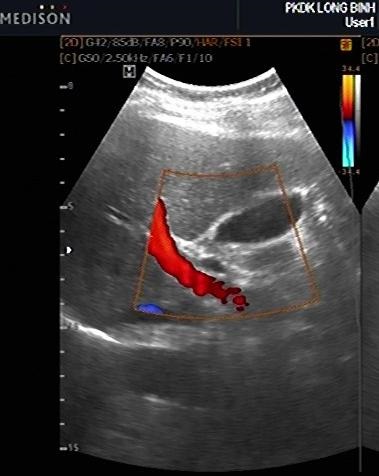

Coupe intercostale de

la ligne axilaire anterieuse droit ( long sagitale -

vesiculaire ) avec technique de encoder de la

difference vitesse du flux sanguine , artere

hepatique est en vue tres nette paralellique au

dessus de la branche droit de la veine porte .

Sa diametre est moins de 5mm |

Flux de artere hepatique est

alternative systole - diastole |